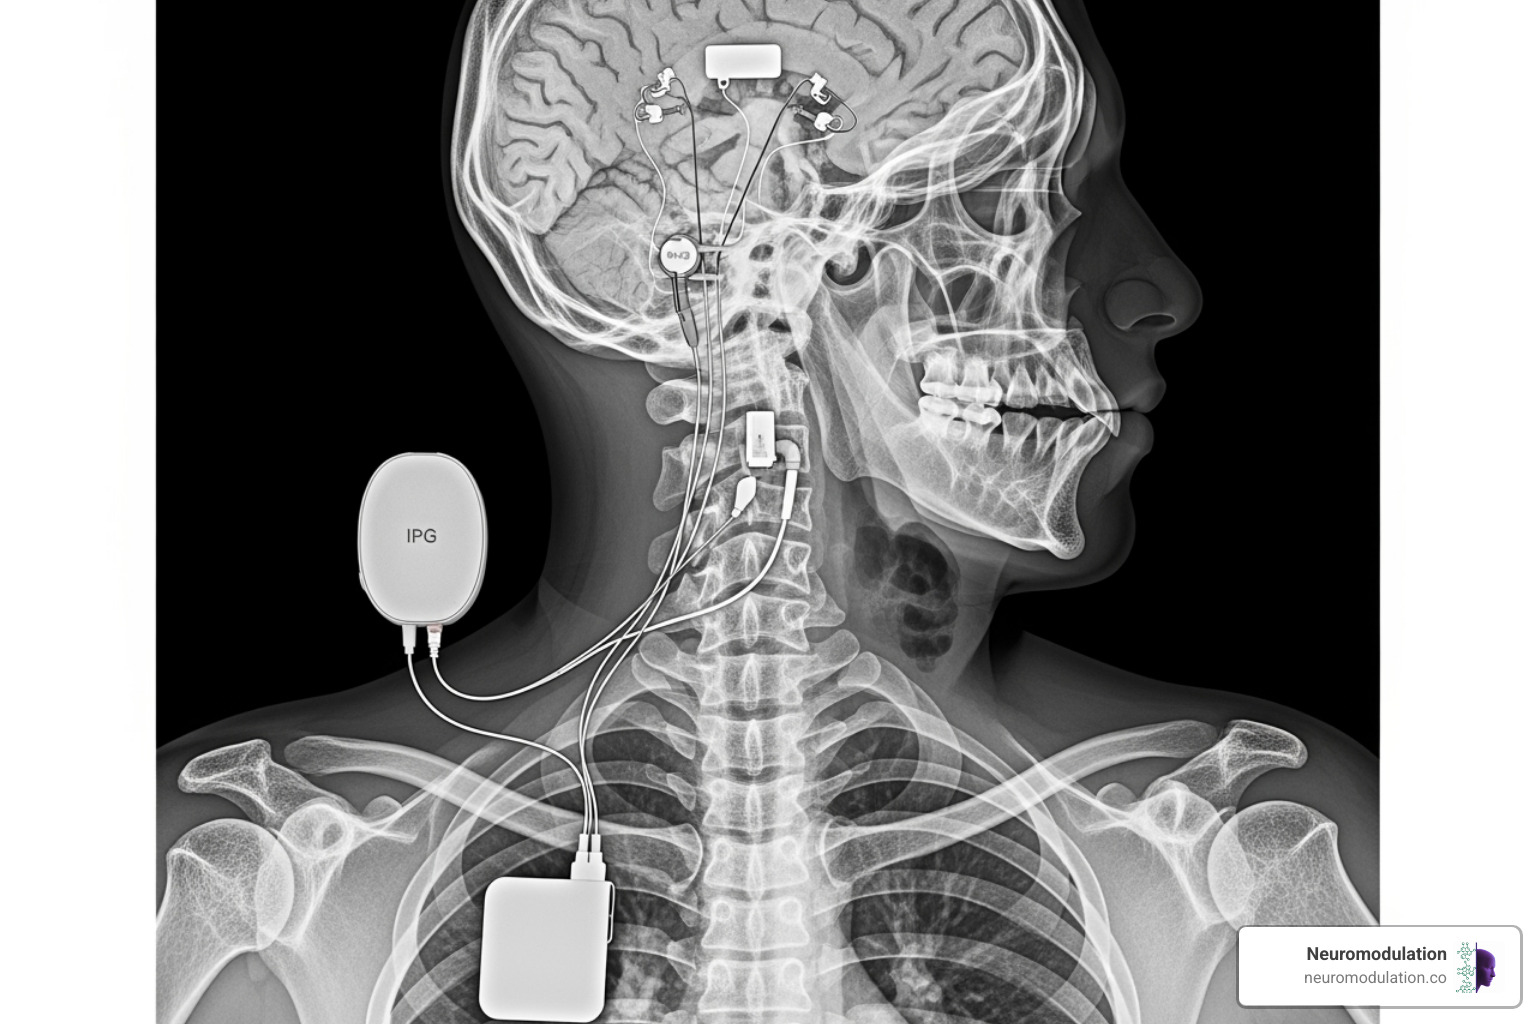

Your DBS system has three main hardware components that could potentially cause problems. The leads are the thin electrodes placed in your brain, the extension wires run from your head down to your chest, and the implantable pulse generator (IPG) is your battery pack, usually tucked under the skin near your collarbone.

The most common hardware complications include inaccurate lead placement requiring repositioning (0.6% of cases), lead migration where electrodes shift slightly over time, lead fractures from wear and tear (0.26%), IPG malfunctions when the battery unit fails (0.26%), and hardware discomfort at the implant site (0.4%). When these problems do occur, they often show up as a gradual or sudden loss of symptom control, or sometimes new side effects that weren’t there before.

Implantable Pulse Generator (IPG) and Extension Wire Failures

Your IPG is essentially a sophisticated computer and battery pack rolled into one. While these devices are incredibly reliable, IPG malfunctions do occur in about 0.26% of cases. More commonly, you’ll need battery replacement surgery when your IPG’s power runs low – this happens every 3-5 years for non-rechargeable units or every 15+ years for rechargeable ones.